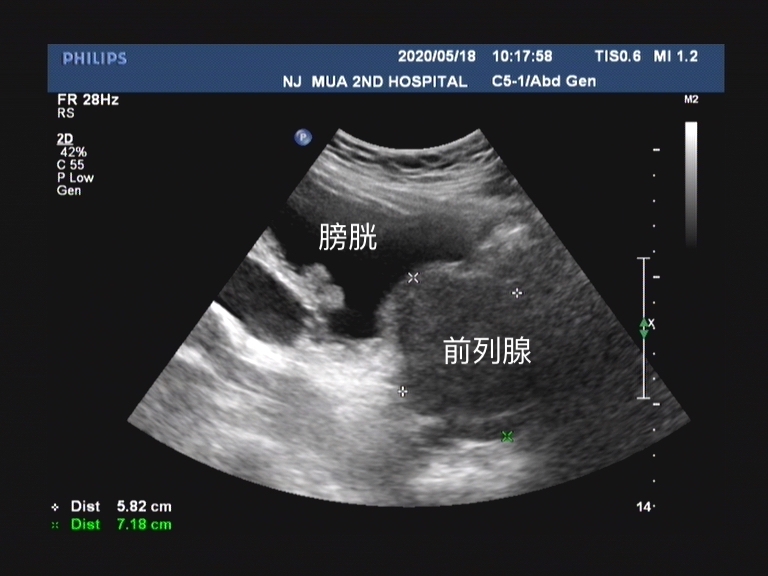

经尿道前列腺电切术适用于体积较小的前列腺增生,临床 推荐主要适用于80ml(0.52*前后径*左右径*上下径)以下的前列腺增生患者 。通过单级高频电热能汽化电切,温度可高达400℃。

这是一种手术操作的技术革新, 对于超过80ml的大体积前列腺有较好的手术效果 。通过寻找 前列腺的外科包膜 , 将前列腺增生腺体剥离出来,可以尽可能地将增生腺体切除 , 术中出现明显降低,也可缩短手术时间,组织切除率和获取率都可提高。